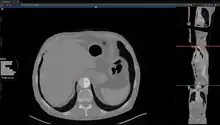

Studierfenster or StudierFenster (SF)[1][2][3] is a free, non-commercial open science client/server-based medical imaging processing online framework. It offers capabilities, like viewing medical data (computed tomography (CT), magnetic resonance imaging (MRI), etc.) in two- and three-dimensional space directly in the standard web browsers, like Google Chrome, Mozilla Firefox, Safari, and Microsoft Edge. Other functionalities are the calculation of medical metrics (dice score[4] and Hausdorff distance[5]), manual slice-by-slice outlining of structures in medical images (segmentation[6][7]), manual placing of (anatomical) landmarks in medical image data, viewing medical data in virtual reality, a facial reconstruction and registration of medical data for augmented reality,[8] one click showcases for COVID-19 and veterinary scans, and a Radiomics module.

Other features of Studierfenster are the automatic cranial implant design with a neural network,[9][10] the inpainting of aortic dissections[11] with a generative adversarial network,[12][13] an automatic aortic landmark detection with deep learning[14] in computed tomography angiography scans, and a GrowCut algorithm implementation for image segmentation.

The file converter converts a medical volume file (e.g. a non-compressed .nrrd file) to a compressed/binary .nrrd file. After the conversion, the compressed .nrrd file can be downloaded and used with the "Medical 3D Viewer" for 2D and 3D visualization, and further image processing.